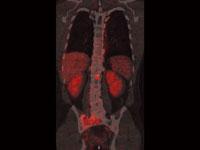

Based in Edinburgh, Scotland, Barco’s Advanced Visualization (AVIS) group is specialized in 3D clinical software solutions, marketed worldwide under the product names ‘Voxar 3D’ and ‘Voxar 3D Enterprise.’ As part of the agreement, TMVS will become the new owner of all AVIS assets, including its full product portfolio. TMVS will help support the development of 3D volume rendering and advanced visualization capabilities for all Toshiba modalities.